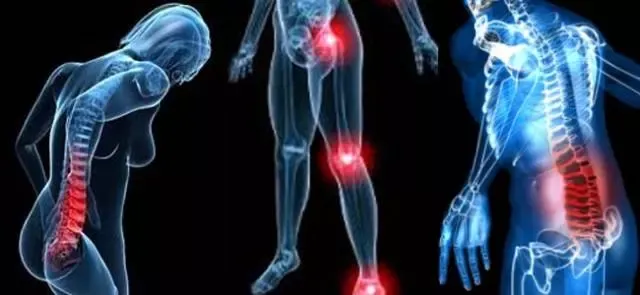

Na Dolenjskem iščete dobro fizioterapijo? Želite učinkovito obravnavo izkušenega fizioterapevta? Potem se obrnite na poslovno enoto podjetja METHOD REBIKA HEALTHY D.O.O. v Novem mestu.

Na naslovu Dolenje Karteljevo 28c, 8000 Novo mesto smo po predhodnem dogovoru dosegljivi, da vam pomagamo pri težavah, katere odpravlja fizioterapevt. To so predvsem:

Kot dober fizioterapevt se na Dolenjskem in v Ljubljani, kjer imamo drugo poslovno enoto, uveljavljamo že dalj časa. Stranke nas rade izberejo, saj zaupajo našemu znanju, izkušnjam, predvsem pa rezultatom kvalitetno opravljene fizioterapije.